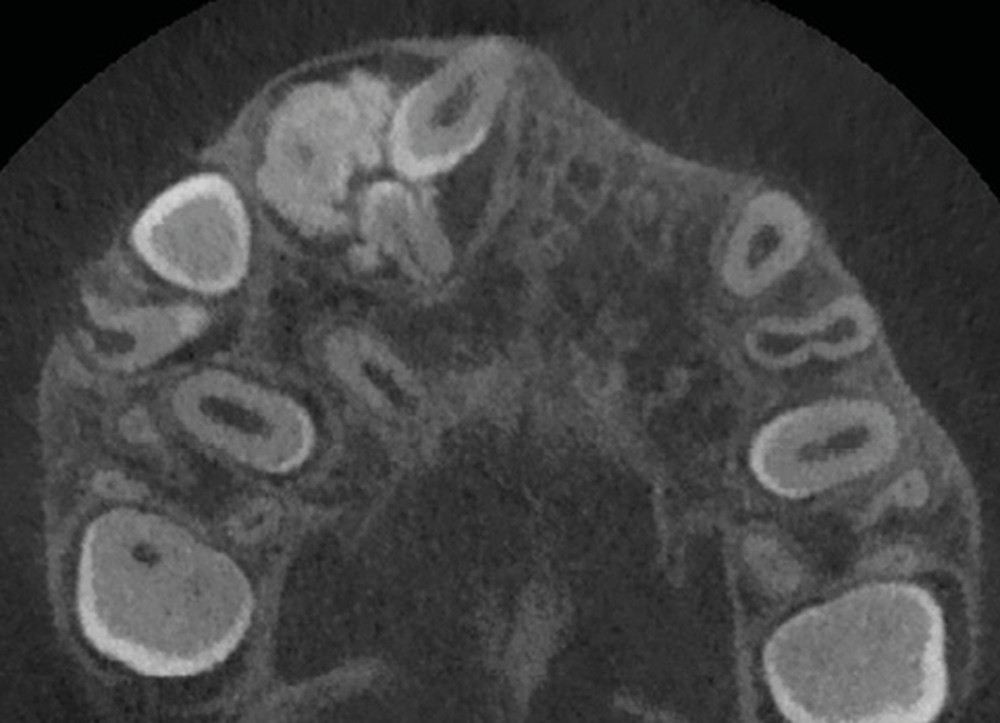

La radiographie panoramique permet une première interprétation de la lésion osseuse (localisation, nombre, taille approximative, etc.). Cet examen est souvent complété par un bilan d’imagerie en trois dimensions de type Cone Beam [4]. Il précisera le volume et les limites de la lésion ainsi que ses rapports avec les structures anatomiques avoisinantes (tableau 1). Ces données radiologiques confrontées à l’examen clinique et à la fréquence relative des lésions permettent de réaliser un diagnostic d’intuition qui orientera la prise en charge.